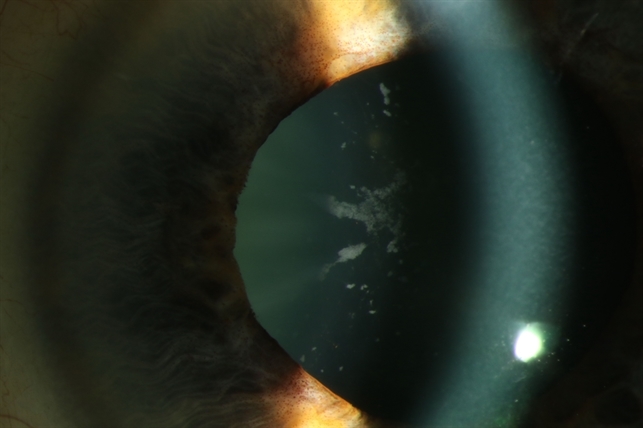

Glaukomflecken are gray white epithelial and anterior cortical lens opacities that occur following an episode of markedly elevated iop as in acute angle closure glaucoma.

These lens changes are caused by necrosis of the lens epithelium. After acute angle closure glaucoma due to pupillary block milky opacities occur underneath the lens capsule. Glaukomflecken is also referred to as cataracta disseminata subepithlias and glaukomatosa acuta. I knew enough about medicine at that point to know that testicles don t typically multiply and a doctor confirmed my suspicion shortly thereafter.

Glaukomflecken under the anterior lens capsule after an attack of acute angle closure. Histopathologically glaukomflecken are composed of necrotic lens epithelial cells and degenerated subepithelial cortex.